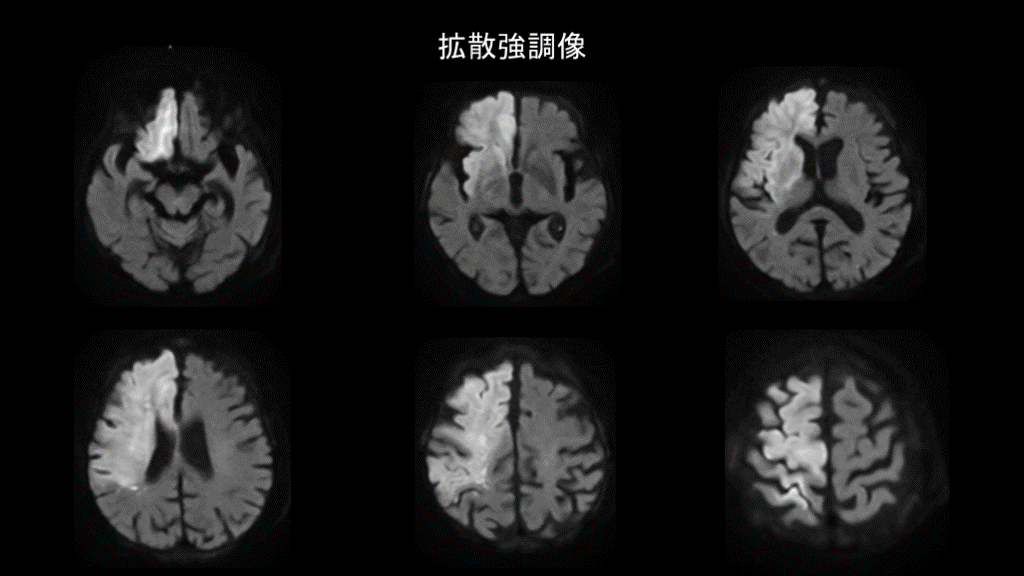

拡散強調像

#17.

症例1 心原性脳塞栓症 ・梗塞範囲が広く皮質まで及んでいる ・主幹動脈が閉塞している ・梗塞範囲が前大脳動脈、中大脳動脈の支配領域に一致する ・心房細動がある 心腔内血栓が内頸動脈を閉塞し広範な脳梗塞をきたした

発症機序と症状の関係